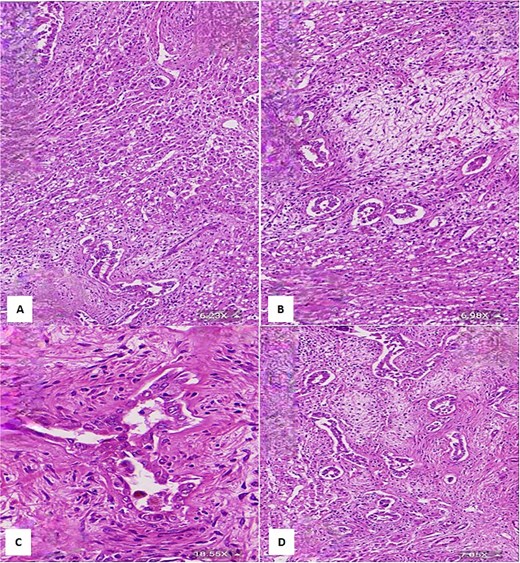

(A & B) Vimentin immunostain demonstrating positive cytoplasmic staining in neoplastic cells (6.26×). (C) CK7 immunostain highlights the benign bile duct epithelium (3.64×). (D) GLUT1 immunostain shows negative staining in neoplastic cells and positive staining in red blood cells (internal control) (11.44×).